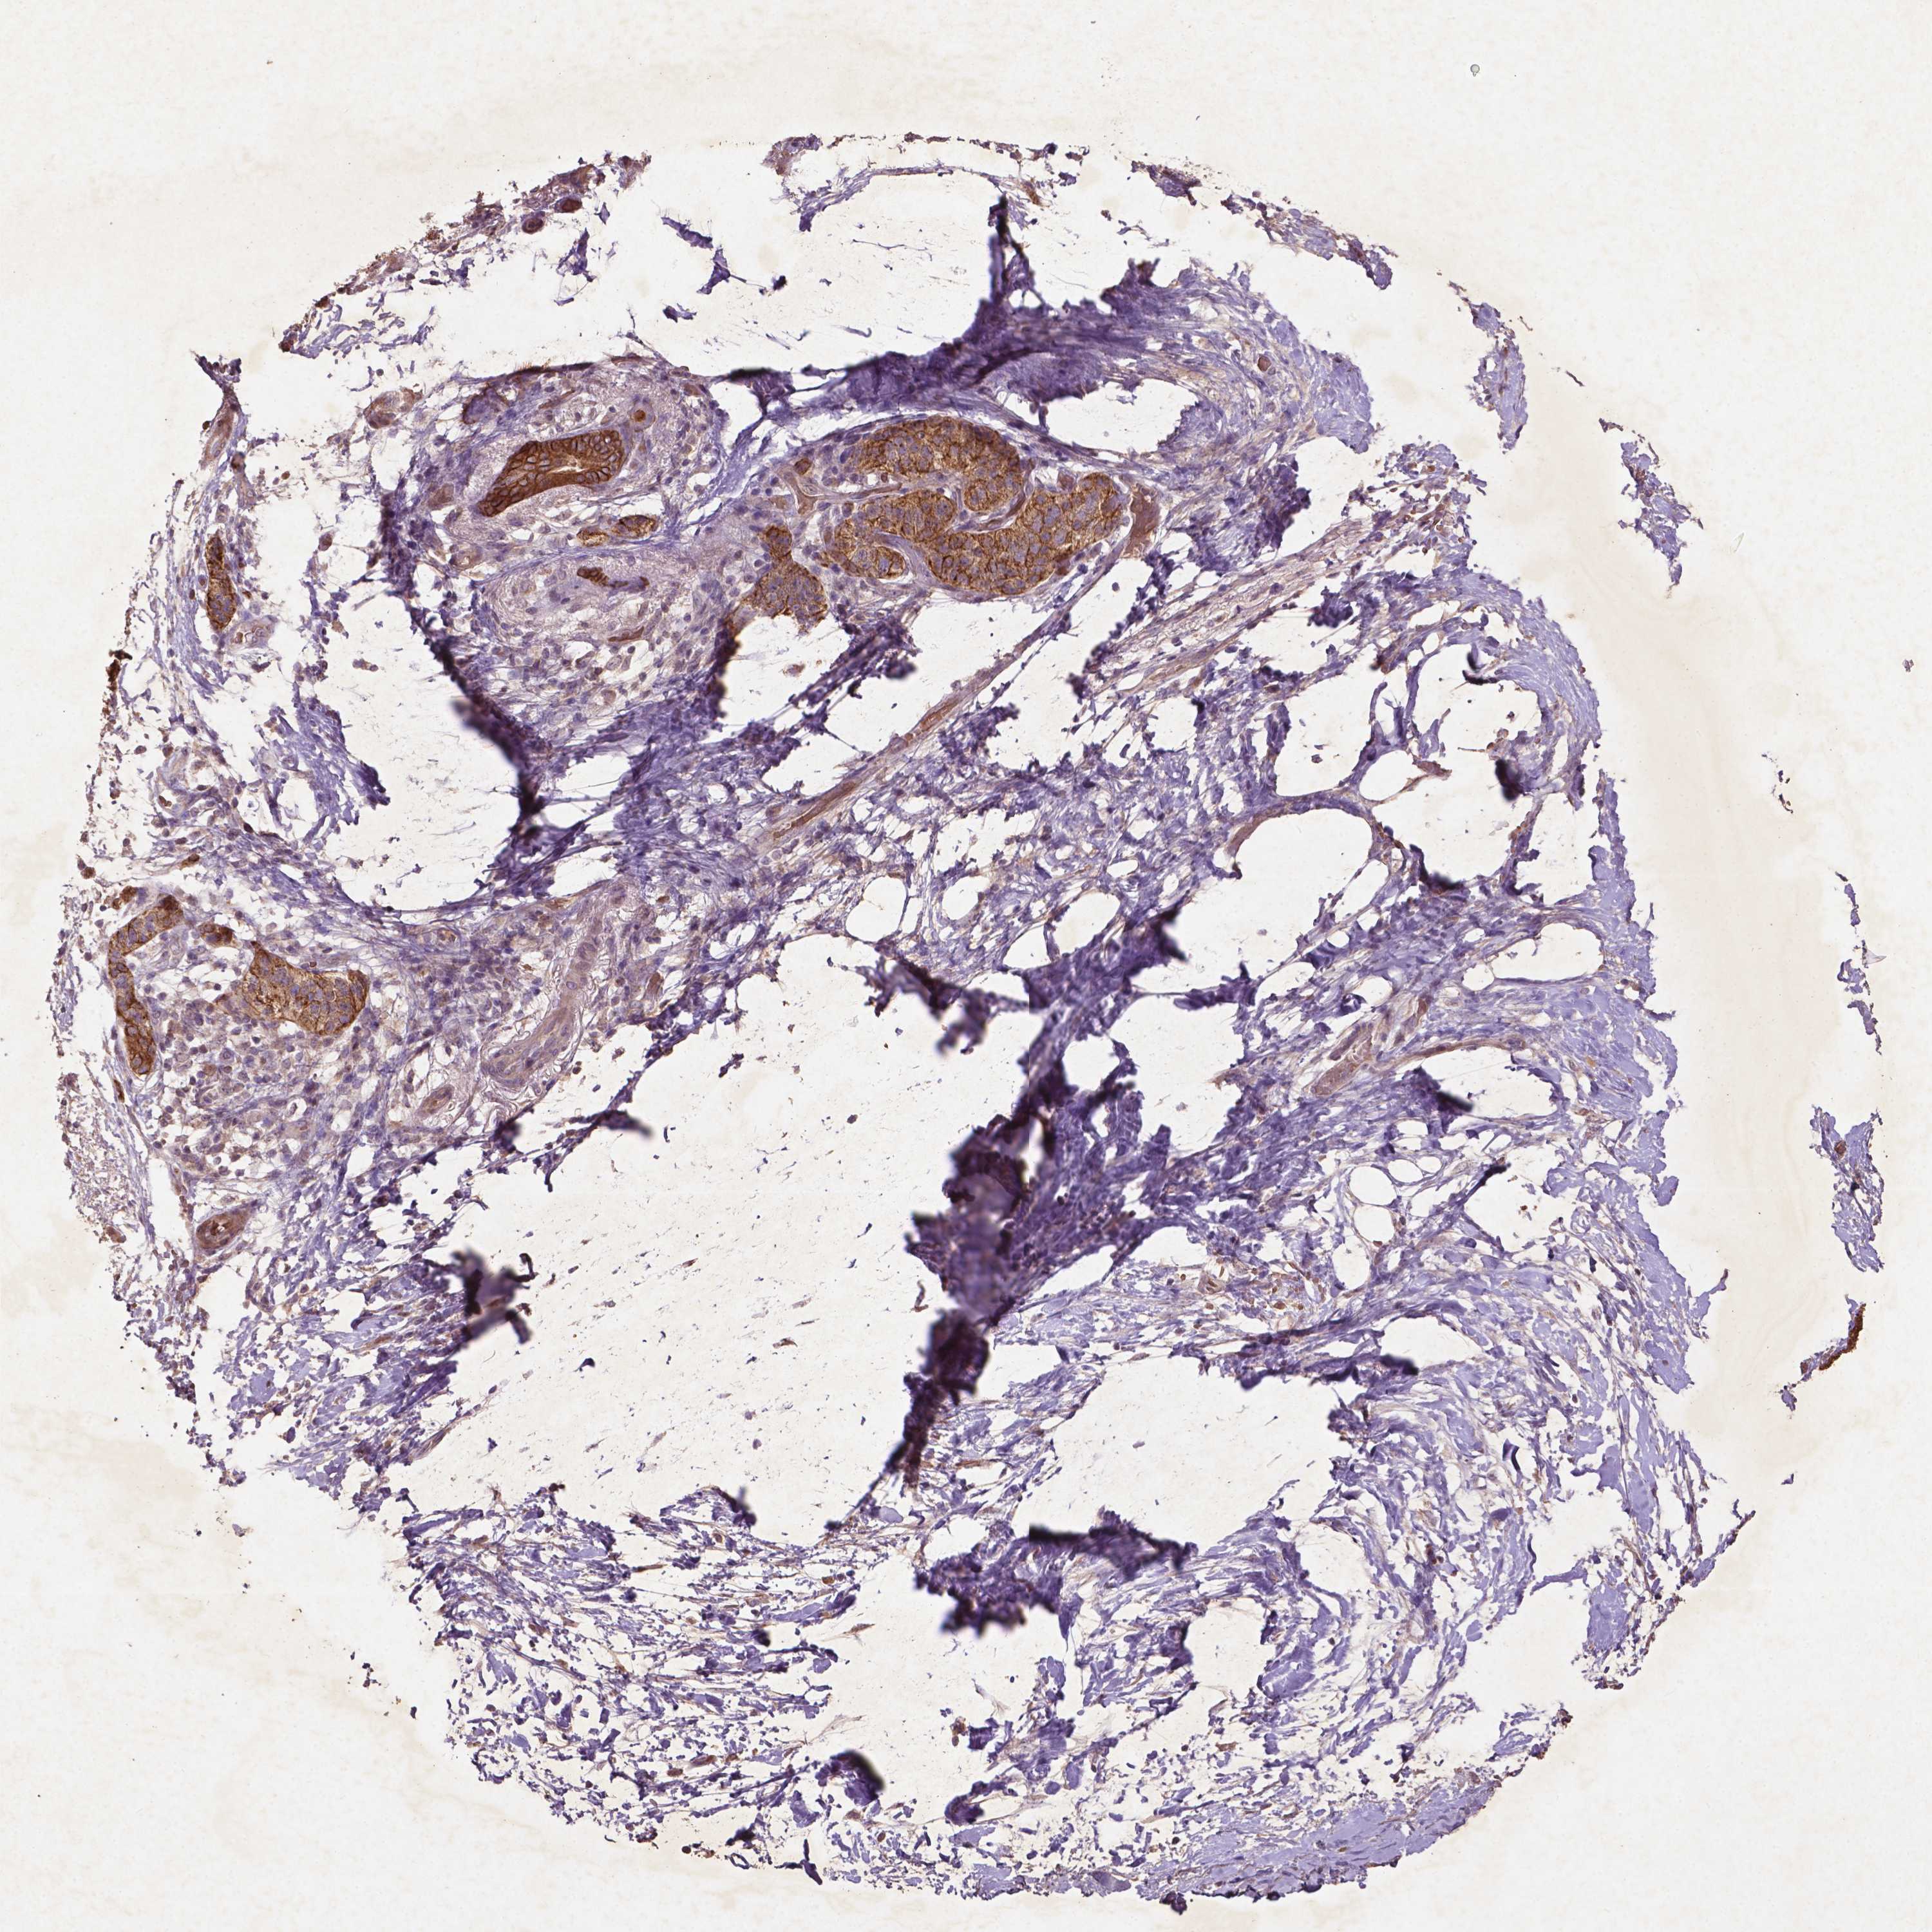

PANCREATIC CANCER - Protein expressioni

A mouse-over function shows sample information and annotation data. Click on an image to view it in a full screen mode. Samples can be filtered based on level of antibody staining by selecting one or several of the following categories: high, medium, low and not detected. The assay and annotation is described here.

Note that samples used for immunohistochemistry by the Human Protein Atlas do not correspond to samples in the TCGA dataset.

Antibody stainingi

Antibody staining in the annotated cell types in the current human tissue is reported as not detected, low, medium, or high, based on conventional immunohistochemistry profiling in selected tissues. This score is based on the combination of the staining intensity and fraction of stained cells.

Each image is clickable and will lead to virtual microscopy that enables deeper exploration of all samples and also displays staining intensity scores, fraction scores and subcellular localization as well as patient and tissue information for each sample.

Antibody HPA068727

Staining

High

Medium

Low

Not detected

Intensity

Strong

Moderate

Weak

Negative

Quantity

>75%

75%-25%

<25%

None

Location

Nuclear

Cytoplasmic/membranous

Cytoplasmic/membranous,nuclear

Adenocarcinoma, NOS